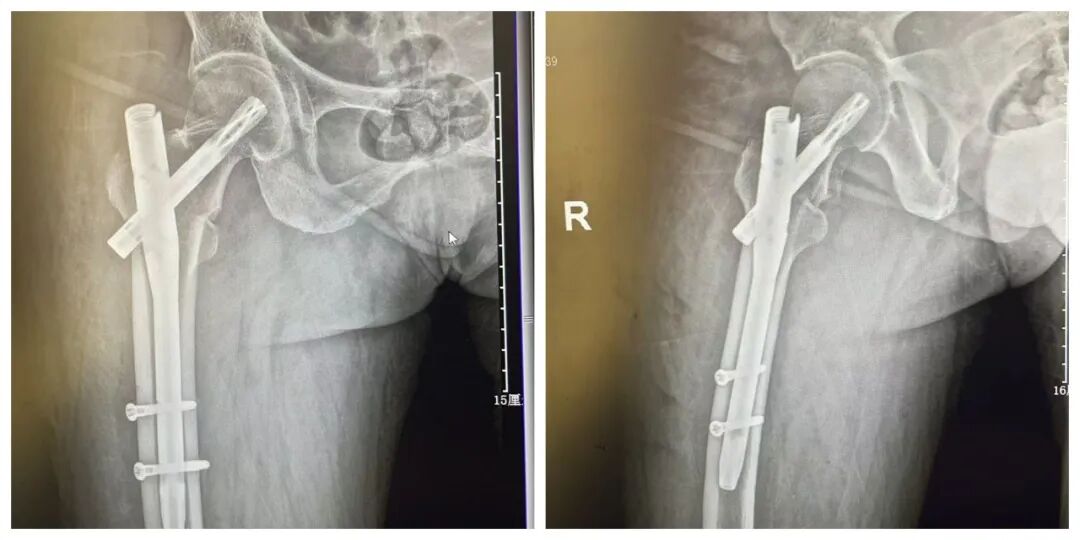

患者术前影像

门诊CT 检查结果明确:右股骨粗隆间粉碎性骨折。骨科团队结合俞大娘的病史、症状及影像检查,综合评估其身体状况后,同样为其制定了 “闭合复位 PFNA 内固定术” 方案。